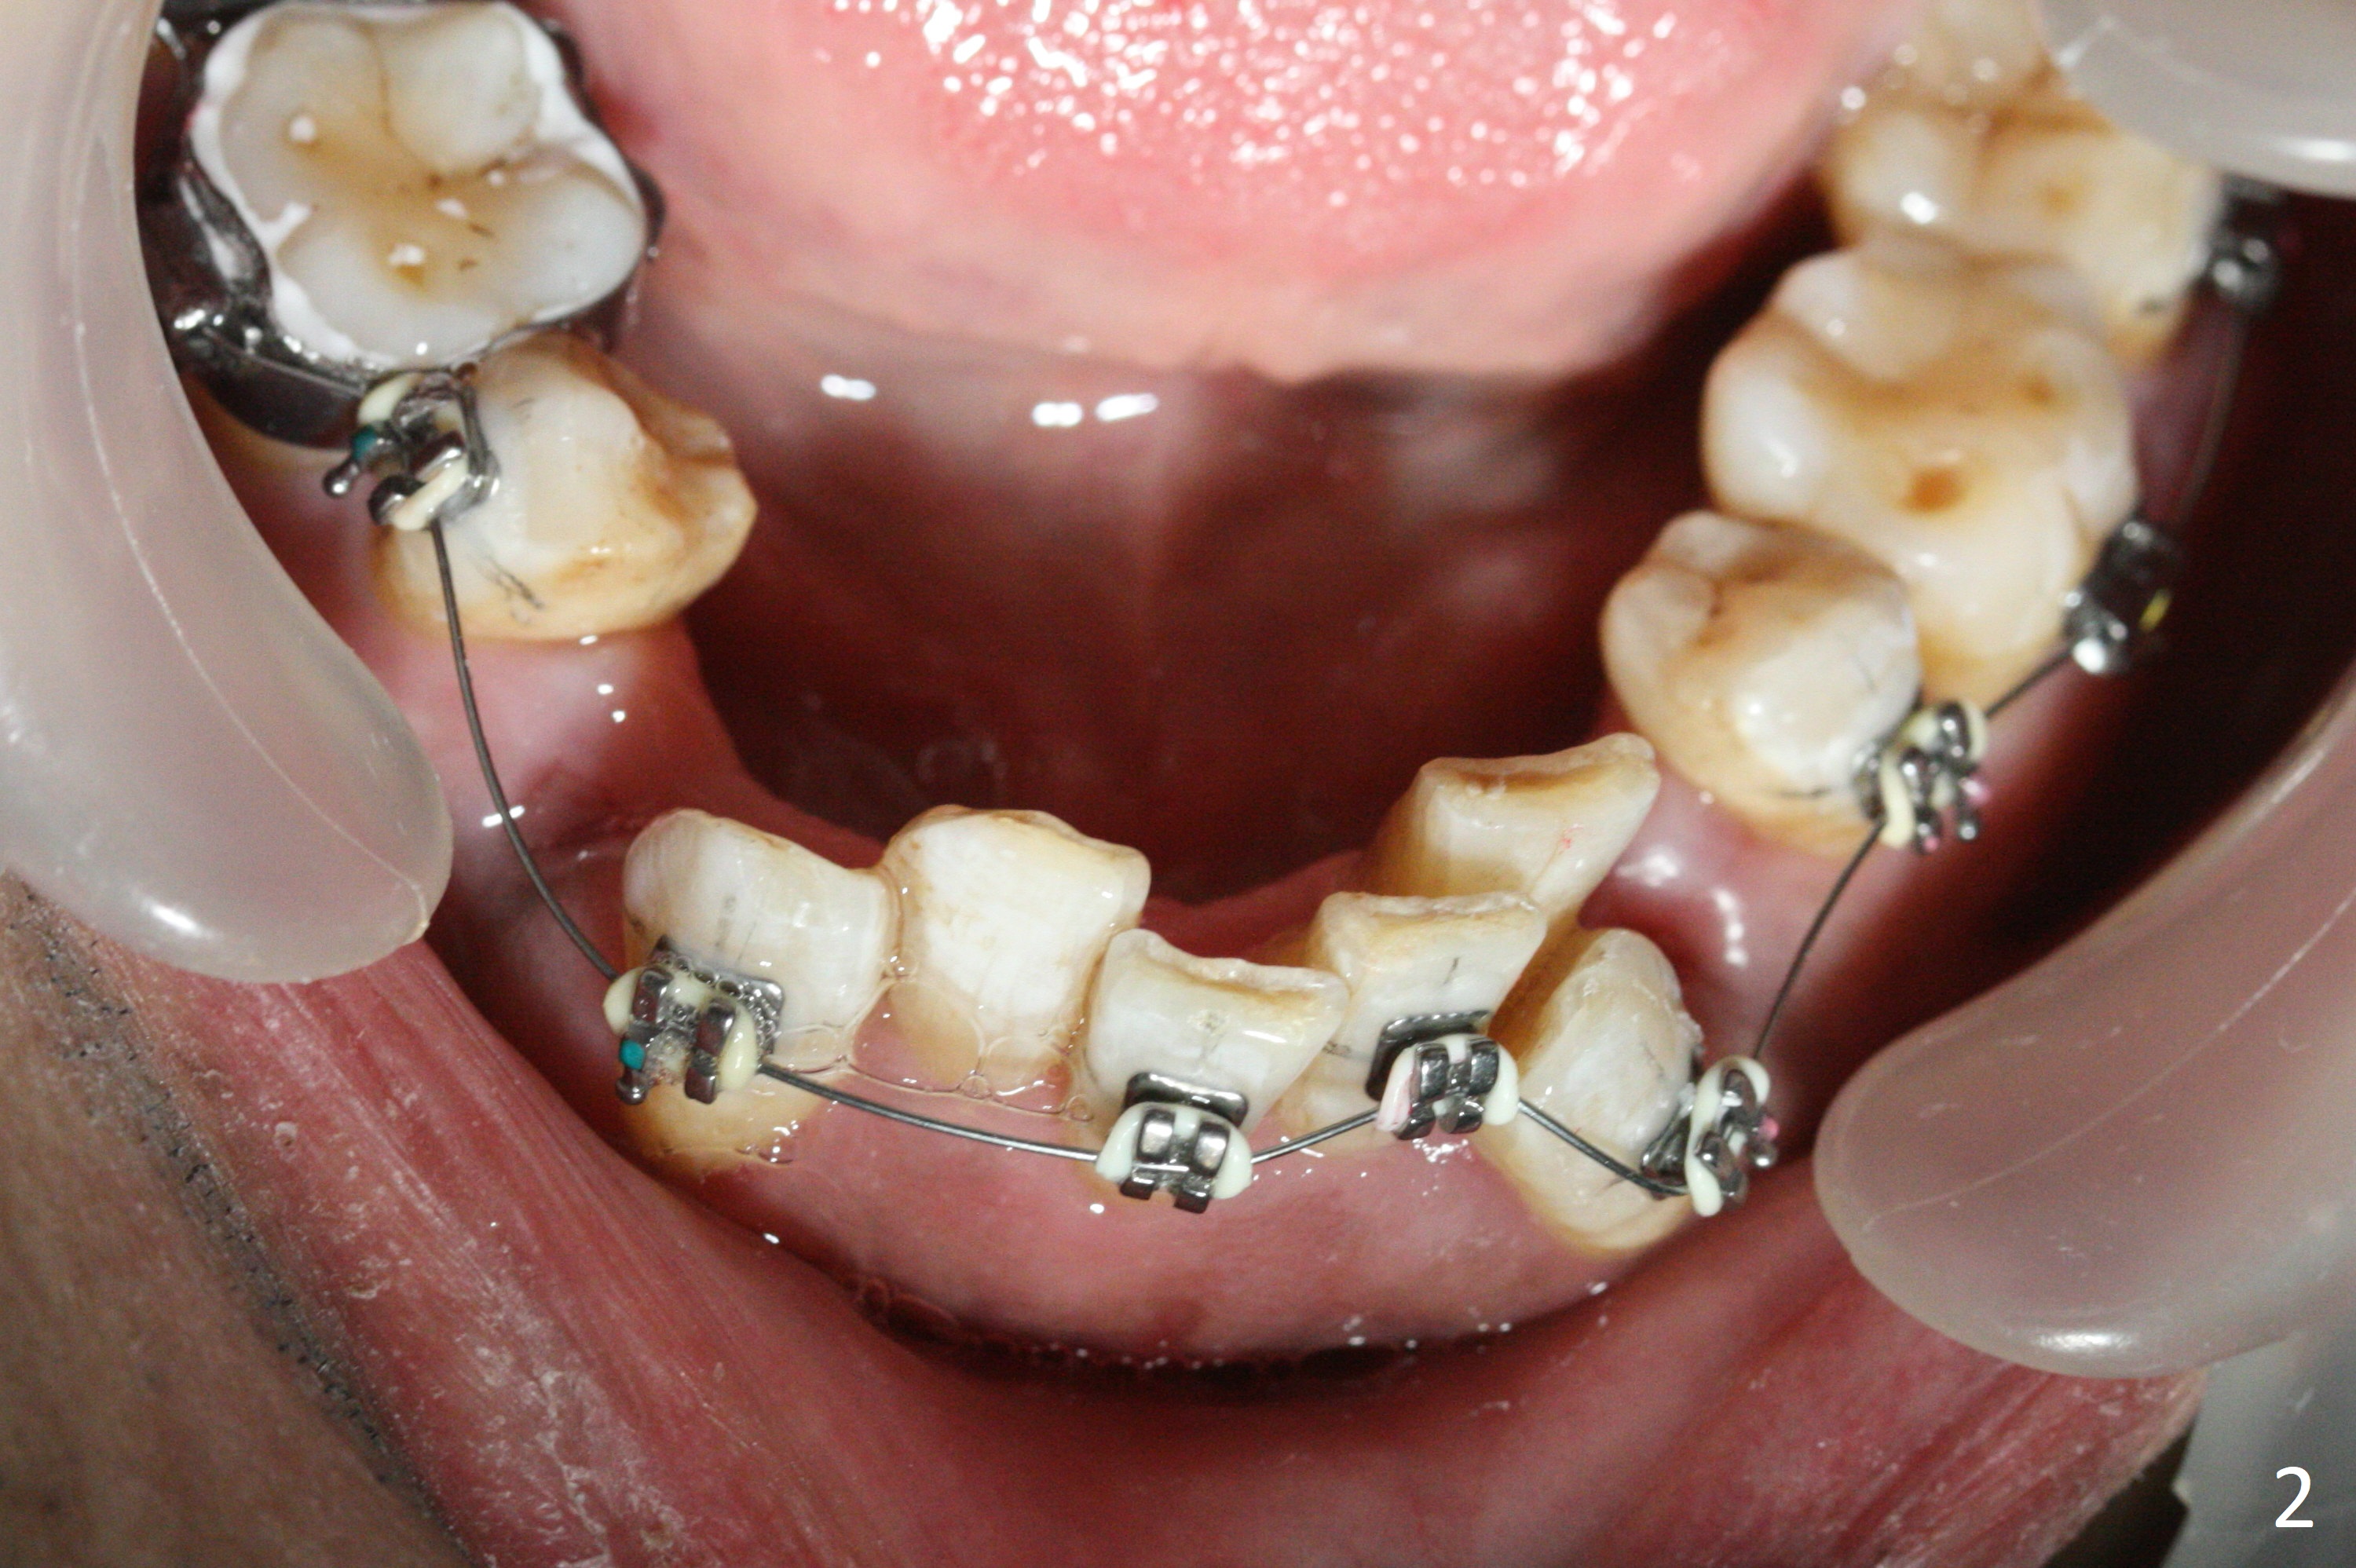

A few days post Water Pik use, the gingival erythema subsides substantially, a sign of cooperation (Fig.1 ^, as compared to earlier). Because of tight contact and loss of rubber separators due to use of water flosser, molar brackets have to be used except LR (Fig.1-3). There is enough space for UR2 bracket 5.5 months post banding. While keeping open and closed springs at UR, place sling shot for UR2. There are 2 purposes. One is to keep expanding the space for UR2, since the sling-shot tends to close the space. The second rationale is to continue mesializing UR1 to correct the upper midline deviation.